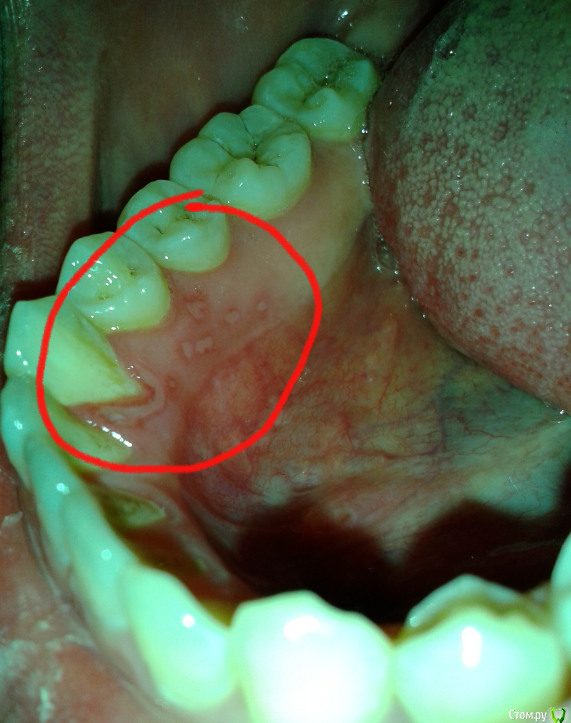

Миха01 Опубликовано 4 декабря, 2014 Поделиться Опубликовано 4 декабря, 2014 2 дня назад оно начел с клыка на 2-ой день до моляров и остановилось 2 дня уже поласкаю ромашкой и мажу метрагилдента стоматолог проверил на камень но нечего не обнаружил что это пожалуйста ваш скорый ответ ? и как лечить ? Ссылка на комментарий

Stomart Опубликовано 4 декабря, 2014 Поделиться Опубликовано 4 декабря, 2014 Болит? Похоже на стоматит. А камень и зубной налет есть. Ссылка на комментарий

shishok Опубликовано 4 декабря, 2014 Поделиться Опубликовано 4 декабря, 2014 Налет и камень видно отчётливо! 1 Ссылка на комментарий

shishok Опубликовано 5 декабря, 2014 Поделиться Опубликовано 5 декабря, 2014 В любом случае необходима профессиональная гигиена у стоматолога(снятие камней и налёта,полировка зубов).По поводу воспаления на слизистой:полоскания любым антисептиком(начиная от фурацилина,хлоргексидина,отвара ромашки,шалфея и тд и тп)+ обработка пораженных участком заживляющими препаратами(напр.солкосерилом).При необходимости-санация полости рта.Как-то так. Ссылка на комментарий